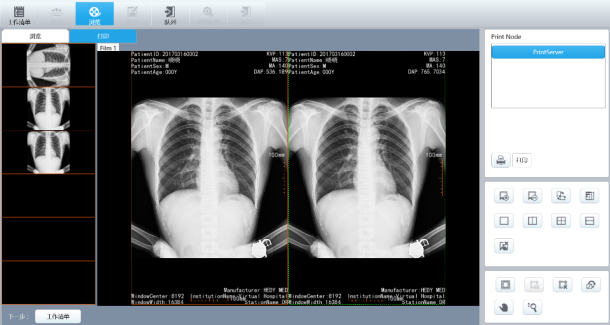

三:一体化智能图像采集处理工作站

1、全中文图形化菜单,集登记、摄影**、图像处理及传输、报告打印、胶片打印等功能于一身,集成度高,操作方便。操作得心应手、三维模拟示教系统初学者轻松上手。

四、智能检查工作流程和信息管理

u 支持大批量表格导入病人信息(支持扫码**,身份证识别器)。

u 优化出图速度,提高出图速度。

u 支持大批量导出病人片子(导出后的病人片子文件名要有病人名字)。

u 拍完后自动保存的病人片子按日期文件夹自动归档(如三月十日拍的片子全部保存在2019-03-10文件夹中)。

2.专业的图像处理软件

u 图像回访:缩略图显示,序列回放工具,数字减影回放;

u 图像处理:窗宽/窗位调整,箭头、文字等标注,角度、距离测量,图像缩放、平移、左右翻转、上下翻转、旋转,黑白反转,减影蒙片选择;

u 图像存储:图像实时存储,DICOM图像发送,光盘刻录,导出存储(可选用多种存储格式:Bitmap,JPEG,AVI等直接用于Word及Powerpoint等办公软件,方便医生诊断报告和论文的书写;

u DICOM 3.0:**兼容各品牌激光相机、PACS系统;

u 病历管理:数据库管理,图文报告,支持WORKLIST。